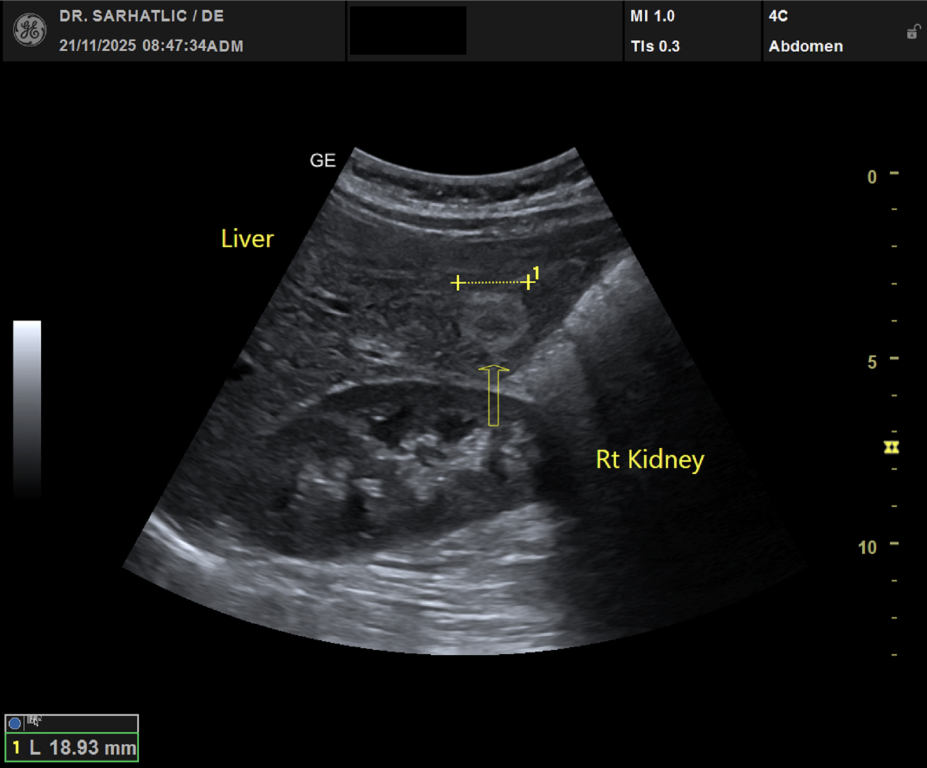

MODERNE ULTRASCHALLDIAGNOSTIK- Modernes Farbdoppler-Ultraschallgerät

- Hochauflösende Schallköpfe

- Detaillierte Organuntersuchungen

- Ultraschall aller inneren Organe (z. B. Leber, Bauchspeicheldrüse, Nieren, Prostata, Schilddrüse)